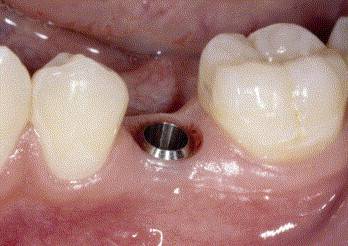

PLACEMENT OF DENTAL IMPALNT

ABUTMENT PLACEMENT